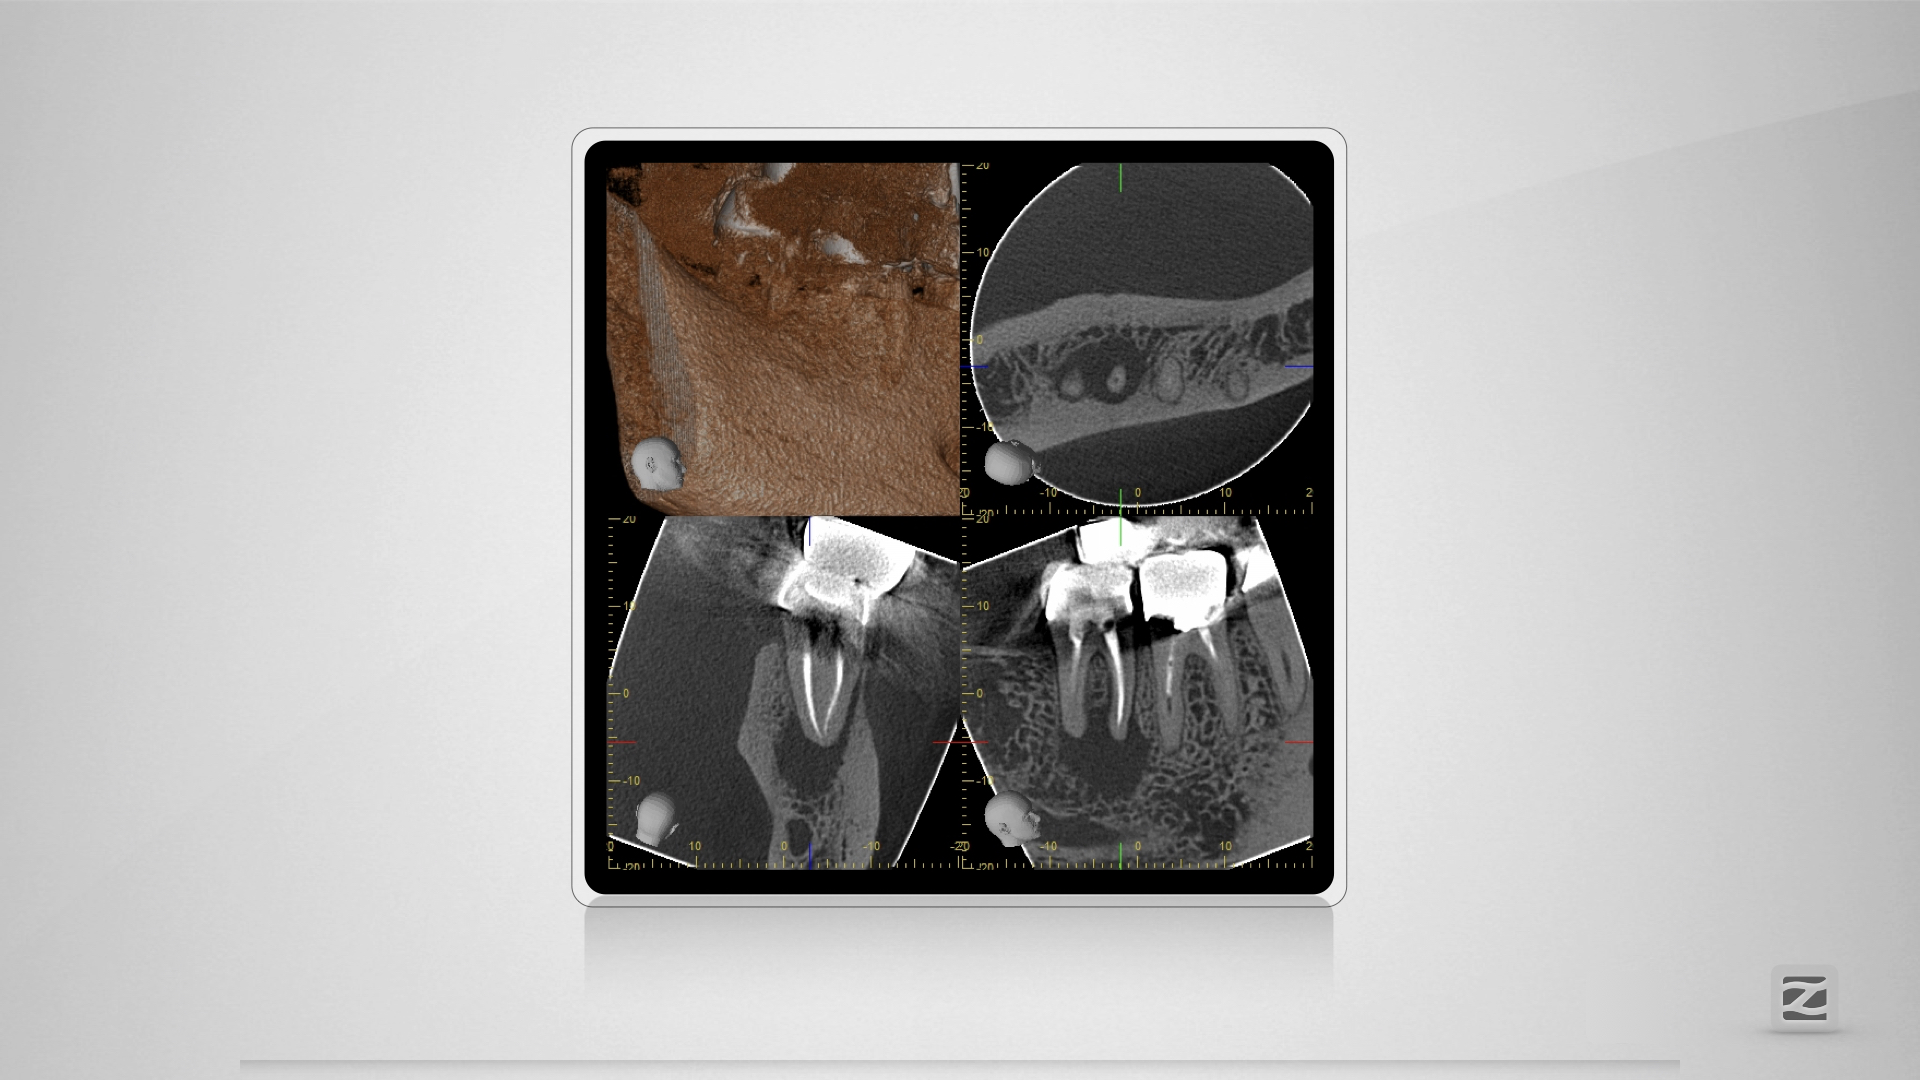

47D.003

1920 × 1080

Kuhfuß